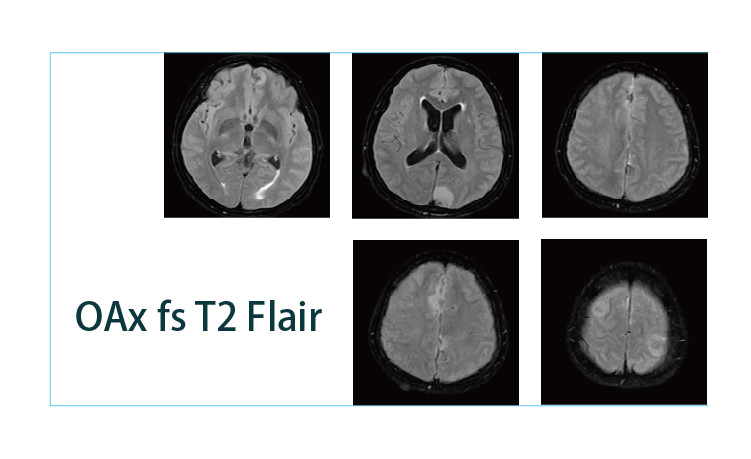

【朗润影像档案】20190426磁共振影像病例结果讨论